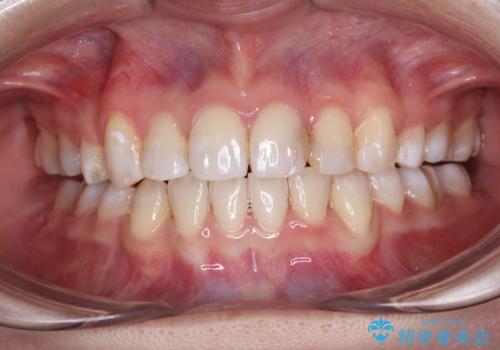

乱れた咬み合わせを治したい 全顎補綴治療

- 今まで通院していた歯科医院では良くなる見込みがないとのことで来院された患者様です。

抜かなければならないほど割れてしまっている歯が放置されていたり、不適合なクラウンが装着されたりと、全体的に多くの問題が散見されました。

インプラントにより奥歯の咬み合わせを安定させ、歯周外科処置などにより歯肉の状態を改善させながら、オールセラミッククラウンにて全顎補綴治療を行うこととしました。

長年通院していた歯科医院では、歯が割れていることに言及してもらうことがなく、当院での診断に初めは驚いていらっしゃいましたが、強い違和感の原因が分かり、かえって安心されていました。

咬む力が強いため、治療の途中で仮歯が外れたり、割れてしまったりと、治療は難航しましたが、奥歯のインプラントが機能し始めた頃から徐々に咬み合わせが落ち着き、前歯も自然な外見のオールセラミッククラウンにて仕上げることができました。

長いこと悩んでいた顎関節の痛みも改善され、患者様には大変満足していただきました。